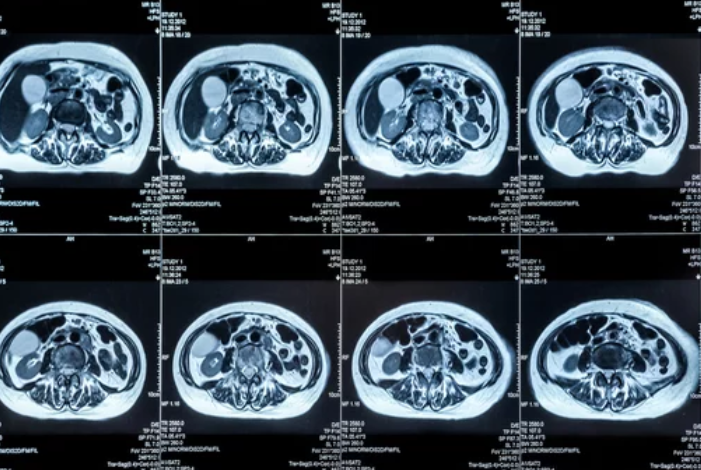

MRI technology has evolved dramatically since its introduction in the 1970s. What began as a slow, noisy process that produced basic black-and-white images has become a highly sophisticated tool capable of mapping the human body in exquisite detail. Modern MRI scanners now deliver high-resolution 3D images, functional insights, and even metabolic data—revolutionizing how diseases are detected and monitored.

This evolution has been fueled by innovations such as AI-assisted imaging, 3T and 7T MRI systems, and real-time dynamic scanning. These advancements have reduced scan times, improved accuracy, and allowed clinicians to analyze physiological changes rather than just anatomical structures. The result is a technology that not only detects disease but also provides critical insights into how the body functions.